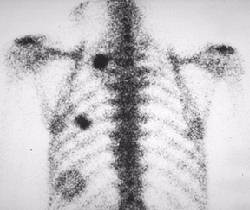

Metastatic OsteosarcomaOsteosarcoma with pulmonary metastases

This bone scintigram in posterior projection demonstrates foci of abnormally increased radiotracer activity in the left hemithorax, in a patient with known osteosarcoma.